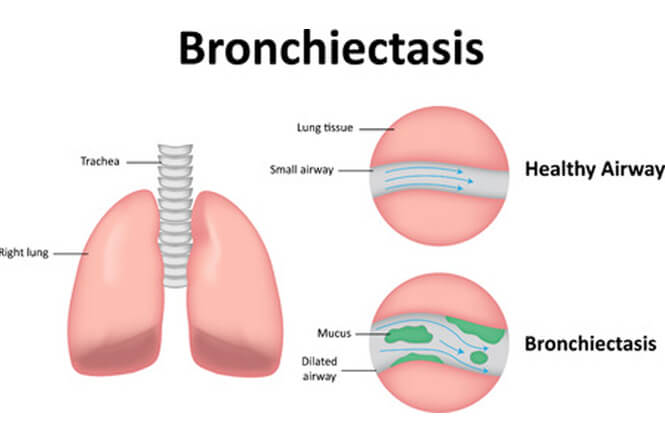

Respiratory diseases

Respiratory diseases are conditions that affect any of the processes involved with breathing. If you or someone you know are one of the 1 in 6 New Zealanders that lives with a respiratory condition, here you can find some useful information on how to manage the condition well.